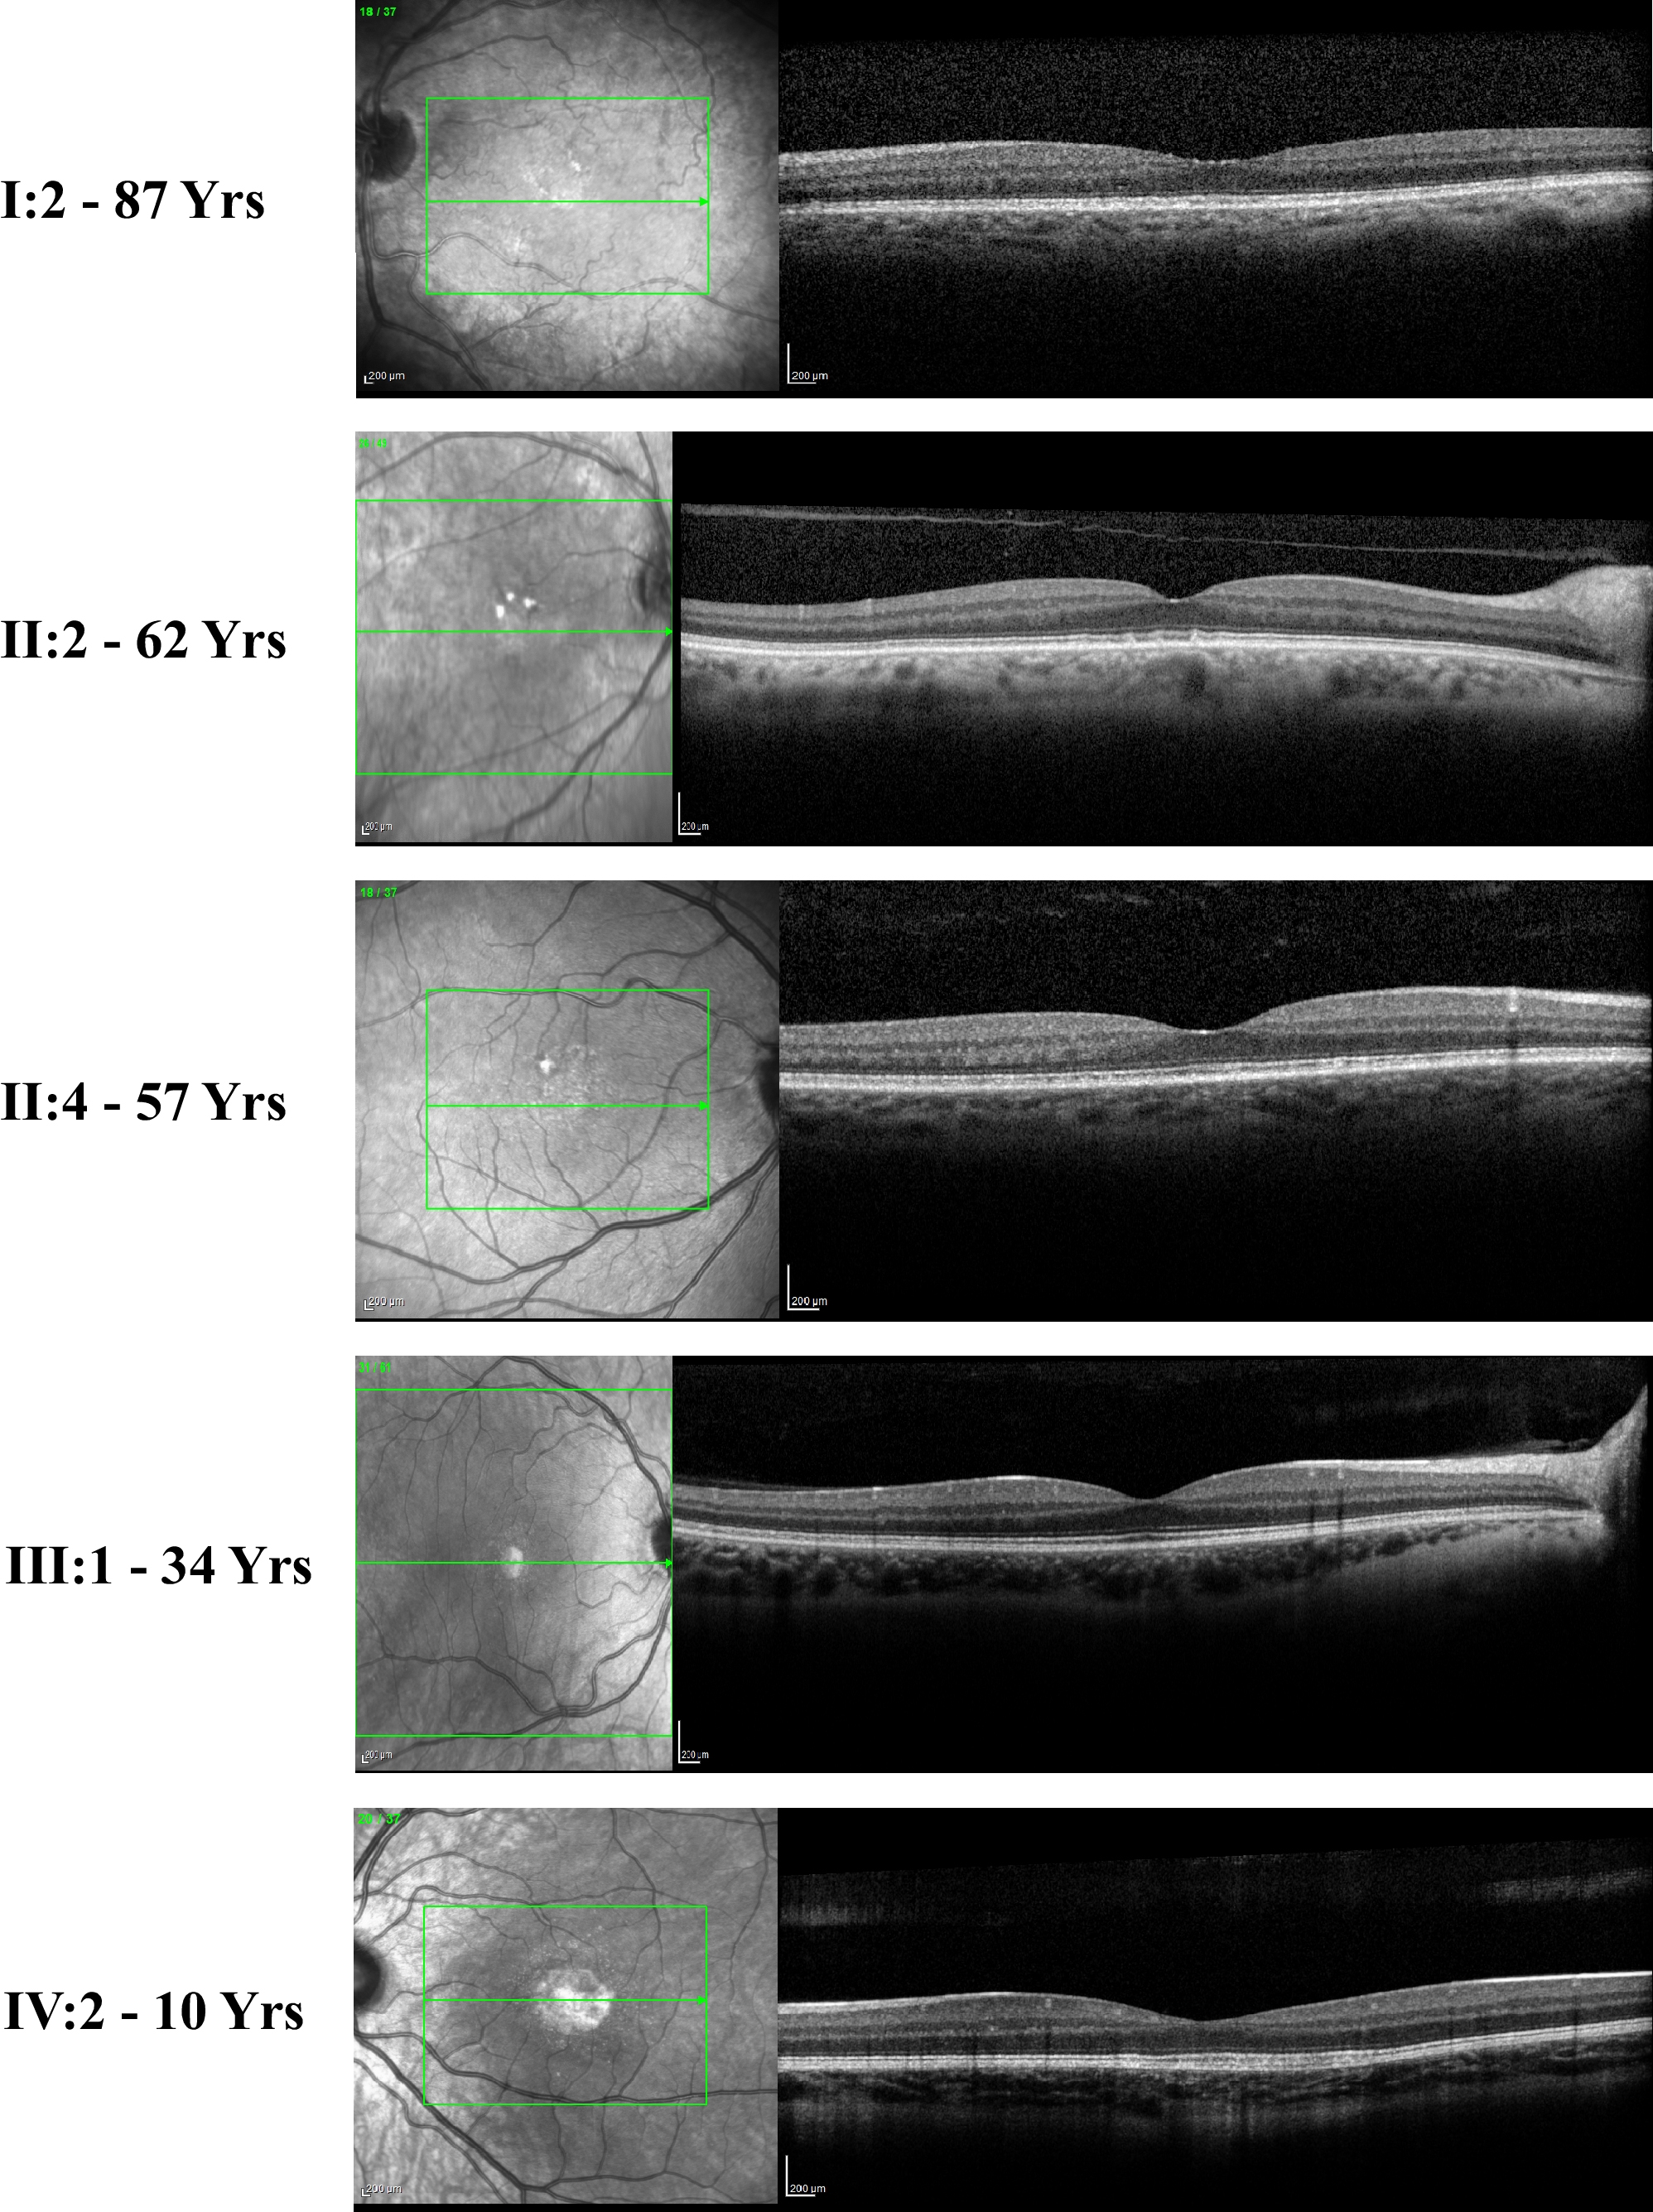

Figure 2. OCT images of affected family members. Representative OCT scans of five affected individuals are shown. Individual numbers

and the age in years are shown on the left. MOL1154 I:2 - preserved inner retinal layer combined with granular interdigitation

layer. MOL1154 II:2 and II:4 - pseudodrusens with intact outer and inner retinal layers. MOL1154 III:1- OCT cross-sections

show normal retinal structure. Note that drusen-like deposits were seen clinically but do not appear in the OCT sections.

MOL1154 IV:2 - subfoveal RPE atrophy combined with thickening of the interdigitation layer, while the ellipsoid layer seems

to be intact.